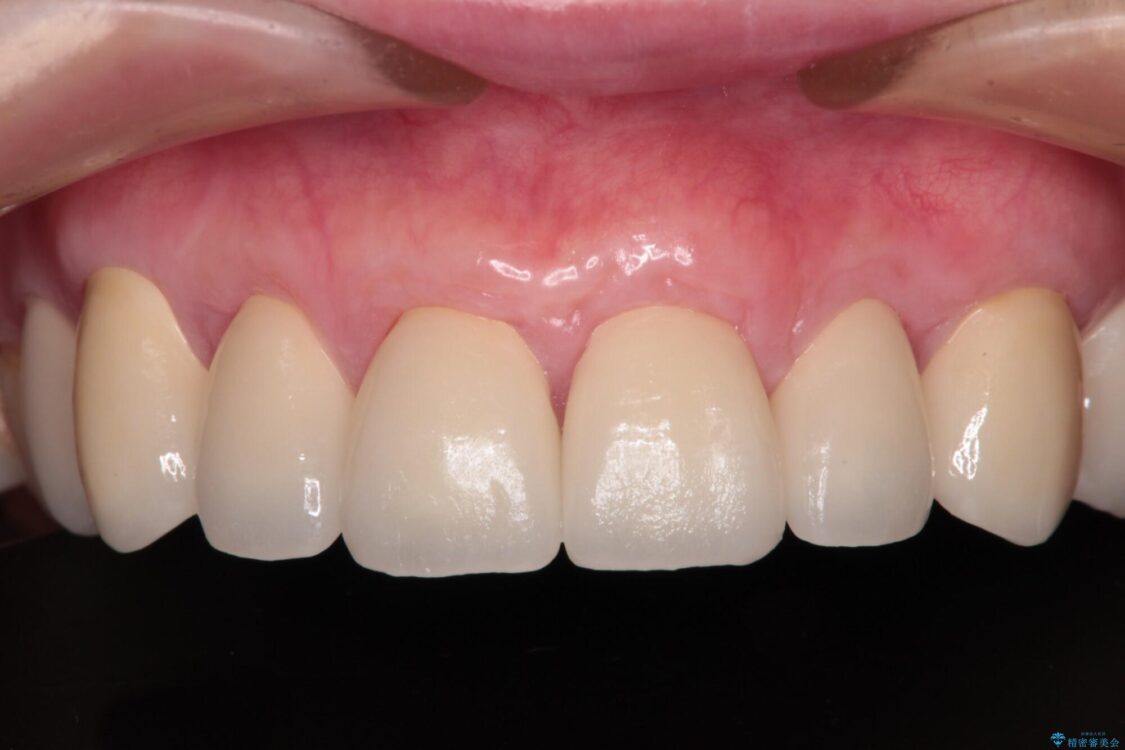

治療後

• むし歯だらけの前歯をオールセラミッククラウンできれいに 治療後画像

治療後について

歯肉移植術による根面被覆を行うかどうかは非常に悩まれていましたが、歯肉が覆われたことで長く見えていた歯の長さが整い、きれいな前歯の仕上がりとなりました。

上顎前歯は歯肉退縮により歯根が露出していたため、事前に歯肉移植術により根面被覆を行い、その後にオールセラミッククラウンを装着することとしました。